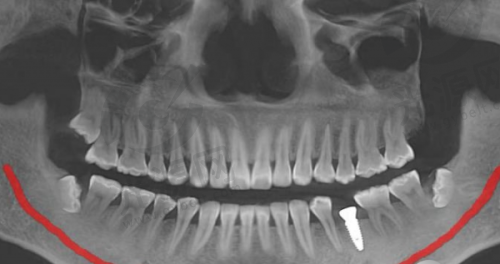

四、唐山地区该项目的技术优势

唐山地区的种植牙技术近年来不断更新,尤其是数字化种植技术和微创种植技术逐渐开始普及。这能有效降低患者的手术风险和修复时间,提高成功几率。